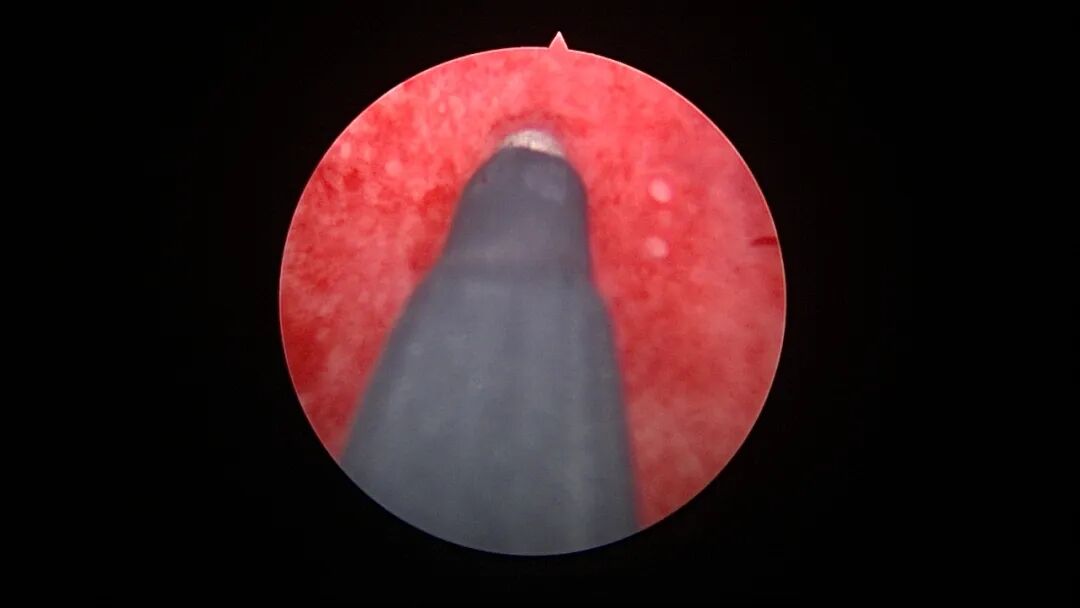

带环受孕图片

带环受孕节育环下移并嵌顿于切口憩室(详见“宫腔镜探秘带环受孕”,好孕空间2023年06月02日发布)

终止妊娠后宫腔很大,固定的节育环就像一叶扁舟